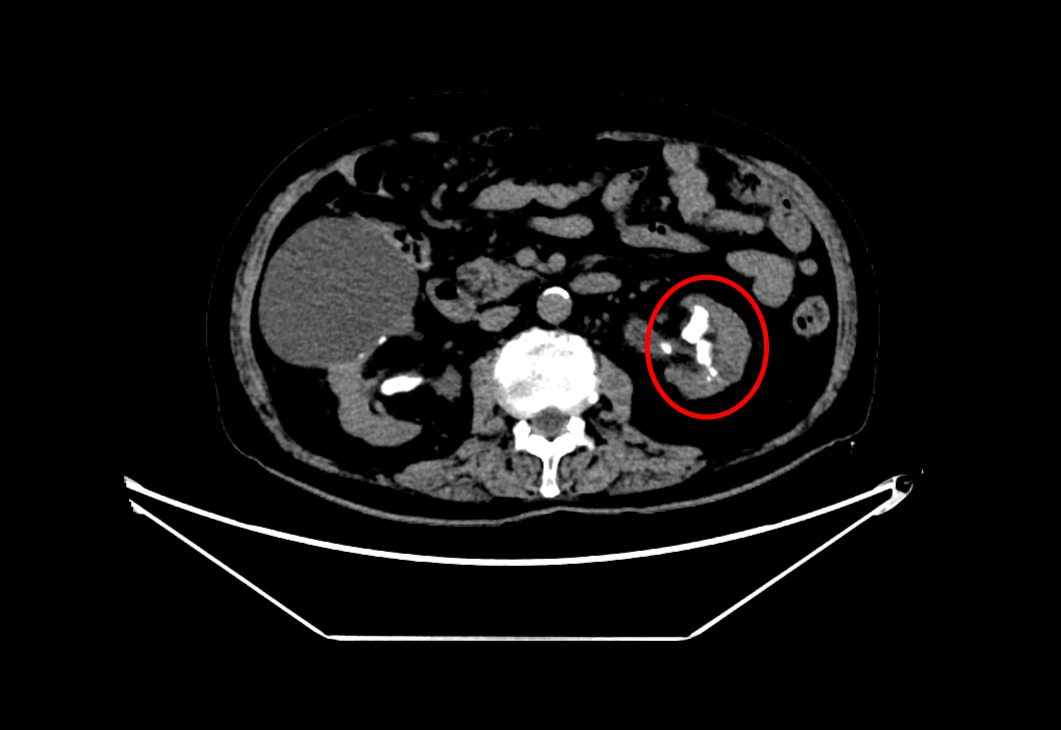

查看详情近日,真人电子网址泌尿外科魏武然主任医师团队成功为一名86岁高龄患者实施“左侧经皮肾镜钬激光碎石取石术+左侧输尿管支架管置入术”。目前患者已顺利康复出院,术后一个月门诊复查...